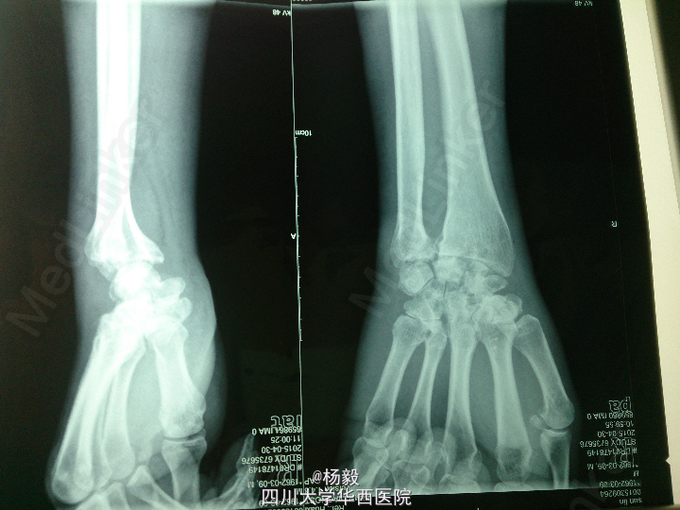

患者男性,50岁,伐木工人,长期托举木材,因右腕关节疼痛2年,加重1月就诊。

影像学如图所示,有部分囊性改变和退变,抽血检查血沉,c反应蛋白,风湿免疫指标均正常

考虑腕关节骨关节炎,建议入院行融合手术。